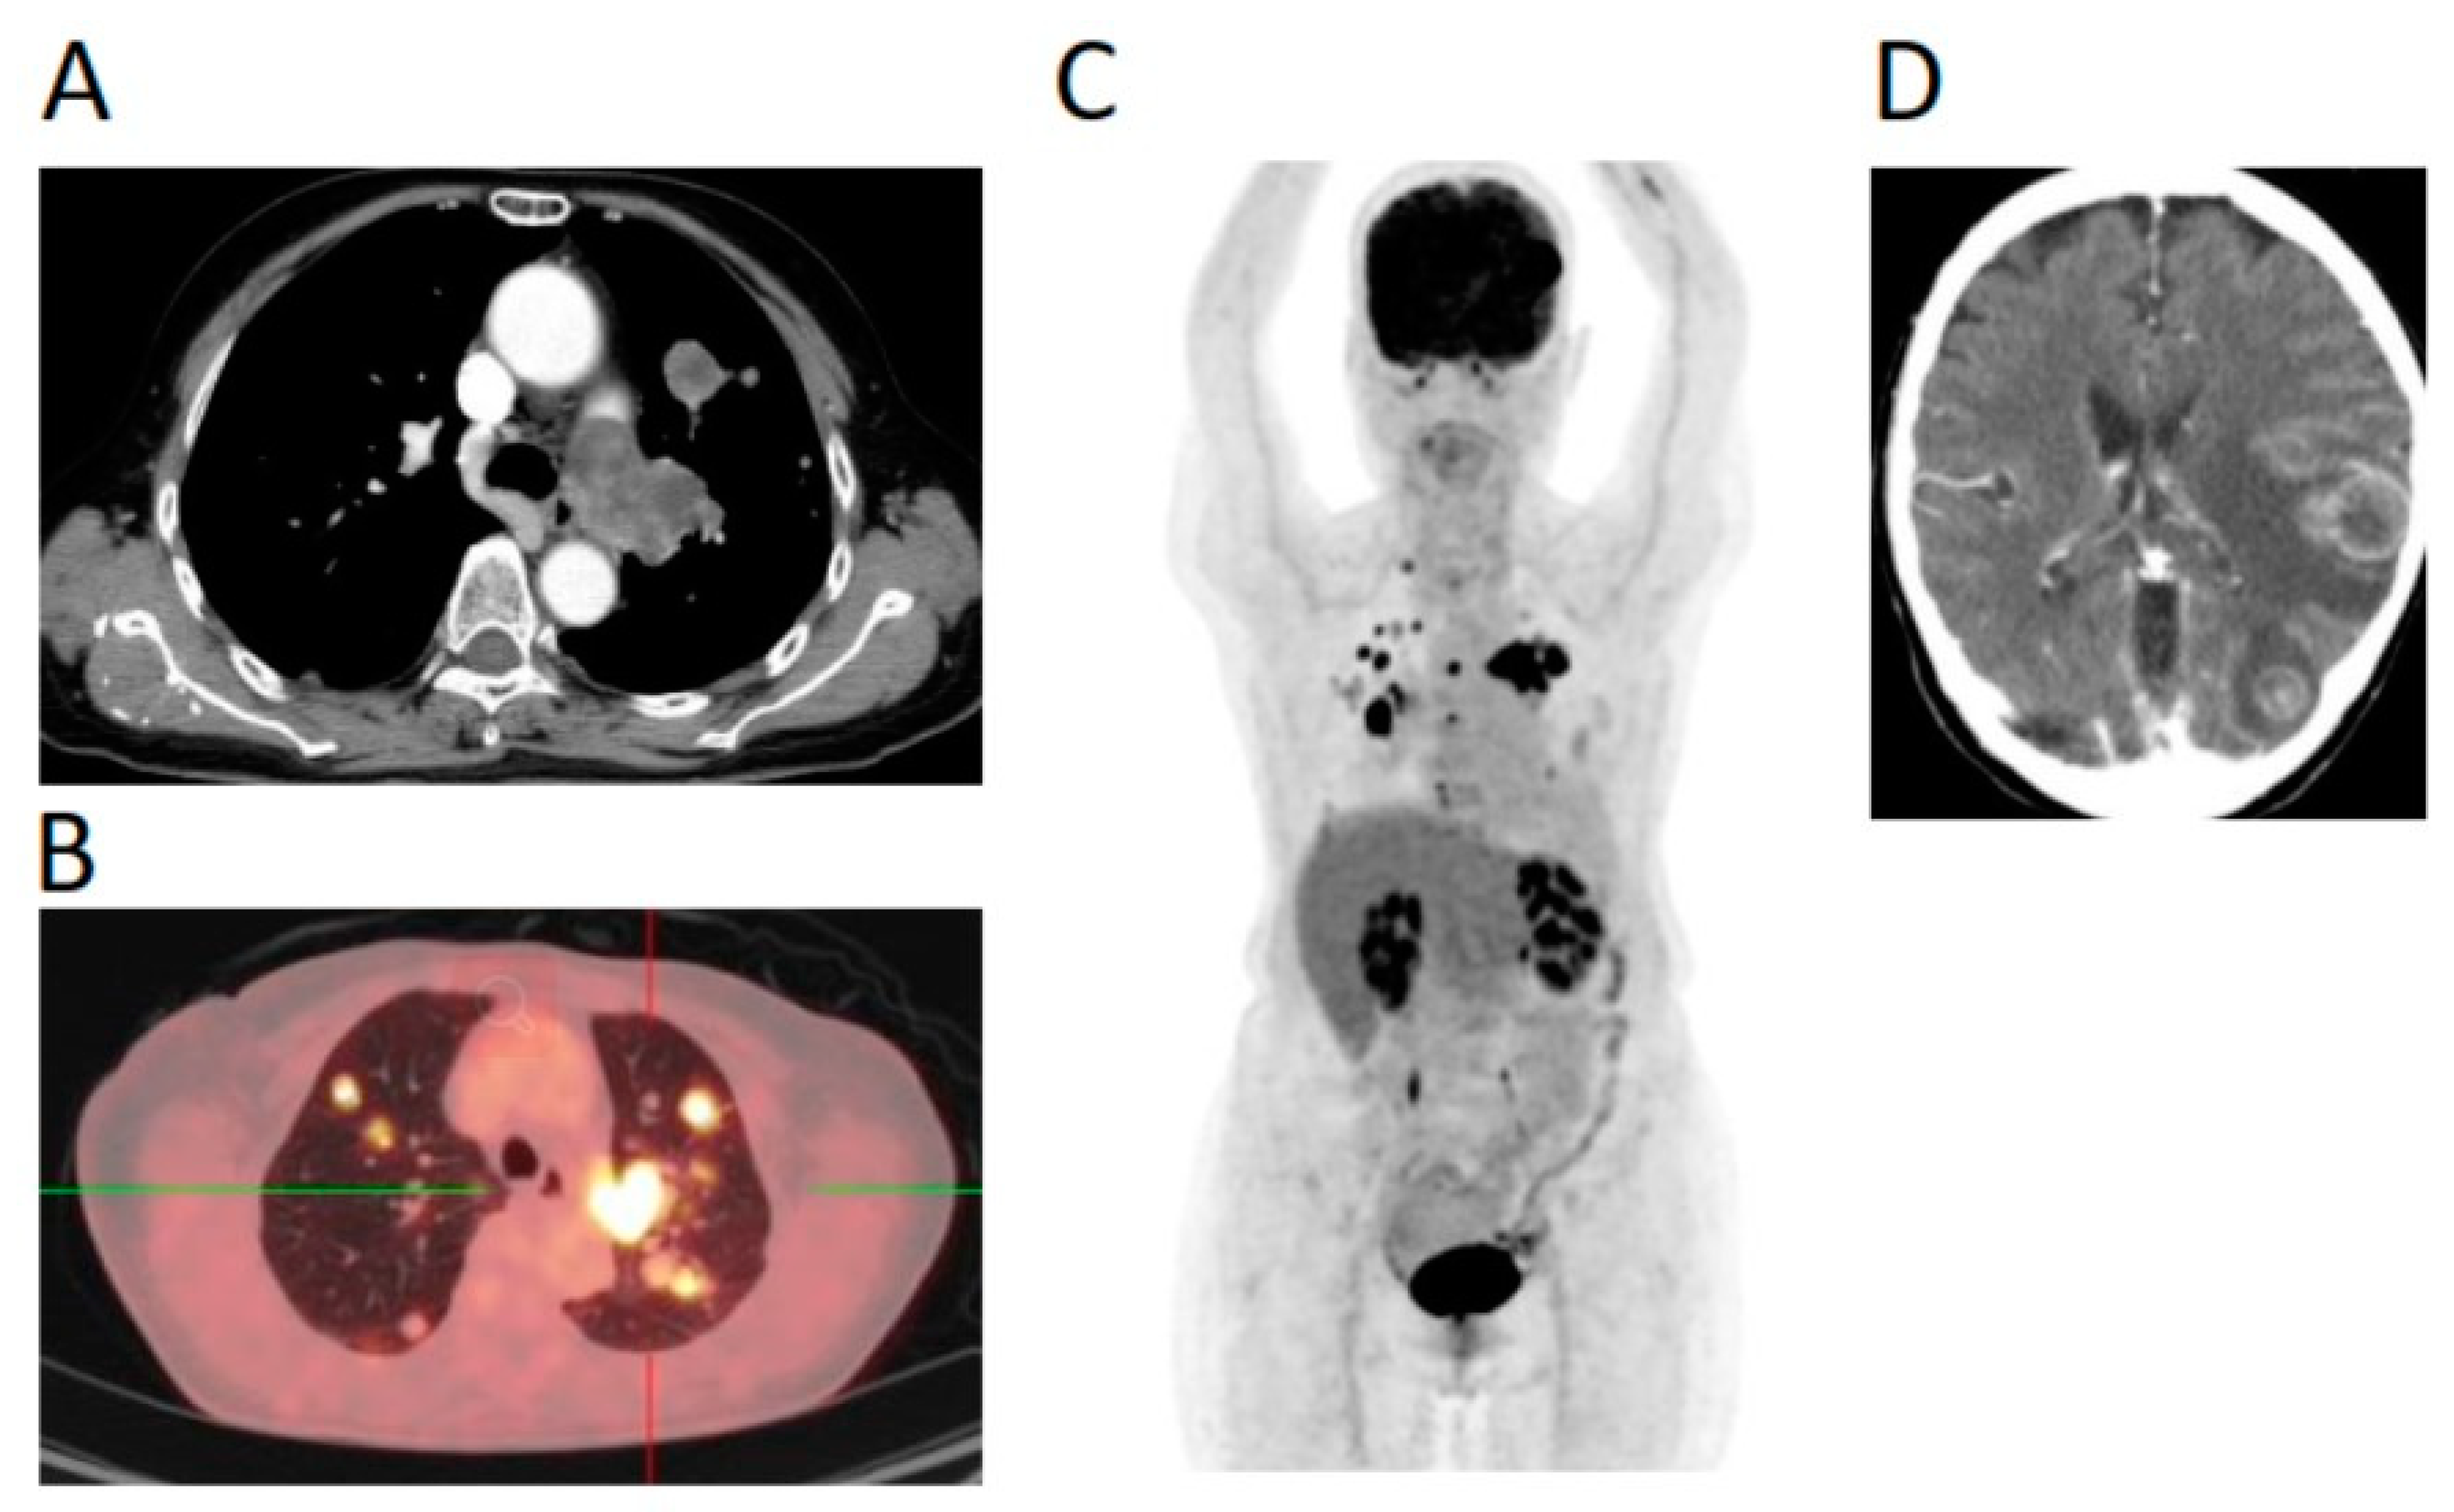

2. Case Report

3. Treatment Course